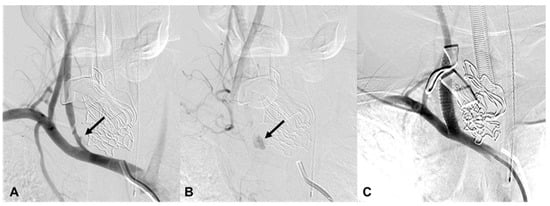

| 6 | 51/F | TA | Epistaxis and oral bleeding | Le fort I fracture | EV, R petrous ICA EV, R ascending pharyngeal | cStent, coil | Stable 423 d F/U |

| 18 | 58/M | Iatrogenic | Oral bleeding | NA | EV, L cervical ICA | cStent | Death 354 d d/t pneumonia |

| 19 | 48/M | Iatrogenic | Epistaxis | NA | EV, L IMA branch | Particle, coil | Stable 2971 d F/U |

| 20 | 34/M | Iatrogenic | Epistaxis | NA | EV, L IMA branch | Particle | Stable 26 d F/U |

| 21 | 23/M | Iatrogenic | Epistaxis | NA | EV, L IMA branch | Coil | Stable 246 d F/U |